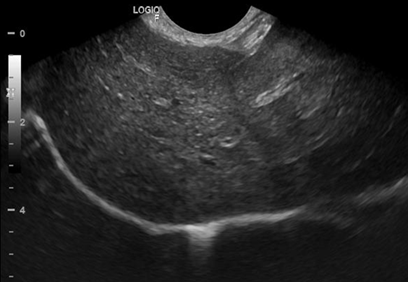

Abdominal ultrasound revealed a decrease in the size of adrenal glands (Figure 2) and hepatosplenomegaly compatible with hepatic steatosis (Figure 3).

Figure 3 Ultrasound of liver. Liver with enlarged dimensions, rounded edges, high echogenicity and coarse echotexture compatible with liver disease/fatty infiltration.